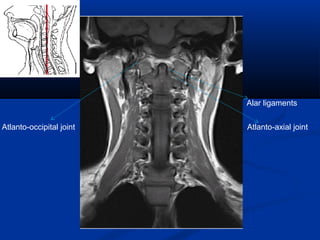

Alar ligaments

Atlanto-axial jointAtlanto-occipital joint